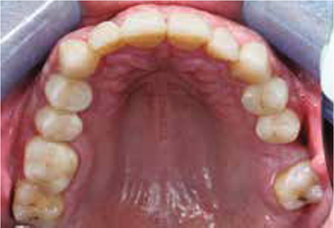

Afb. 3

Occlusaal aanzicht van de bovenkaak.

Bij het extraoraal onderzoek zie ik een lichte hypertrofie van de m. masseter. Intraoraal tref ik een ernstig versleten dentitie aan waarbij de slijtage niet passend bij de leeftijd kan worden genoemd (afbeelding 2-7 en tabel 1) .